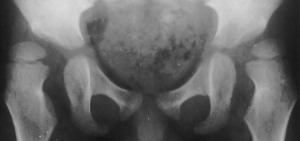

At 4y.+1m., he underwent soft tissue release:fractional lengthening

of proximal part of semitendinosus and biceps ; slide lengthening of semimembranosus;

tenotomy of adductor longus and Gracilis and psoas major; fractional lengthening

of rectus femoris and intermedius. An abduction pillow has been applied

post-operatively. At 6 y.+ 2m. (post-op. 2y.), flex; 140 degrees, abd;

35 degrees,p-angle; 35 degrees bilaterally,Thomas; 10 degrees on the right

and 15 degrees on the left;. The x-ray showed dramatical improvement of

the subluxation and acetabular coverage.